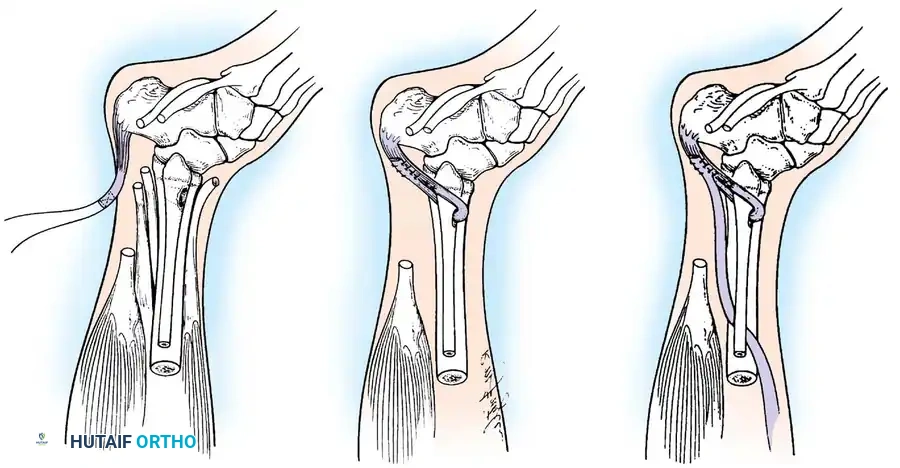

Paralytic Calcaneus:

A devastating deformity resulting from triceps surae paralysis. The unopposed dorsiflexors pull the foot into calcaneus, while the intrinsic muscles and plantar fascia contract, creating a calcaneocavus deformity. Reconstruction requires plantar fascia release, followed by transfer of the tibialis posterior, peroneus longus, and flexor hallucis longus to the os calcis to restore plantarflexion power.

Image